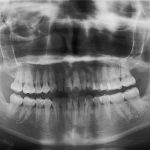

皆さま、こんにちは。 アルデブラン・デンタルクリニック神戸三宮院 歯科助手のYです。 今回は矯正治療の精密検査について詳しくご紹介します。 検査項目は以下となります。 ・レントゲン ・虫歯、歯周病のチェック ・口 […]